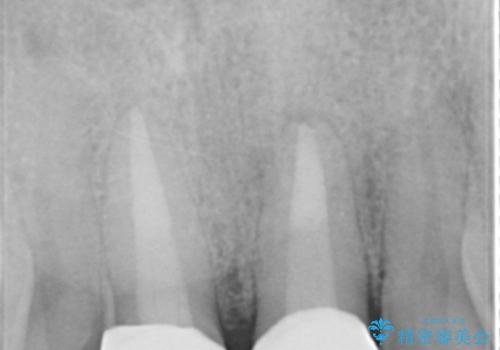

X線写真より、根尖部に透過像が認められ根管治療・ファイバーコア築盛・セラミッククラウンの作製が必要な状態です。

X線検査や歯周組織検査などを行い適切な治療を行うことで良好な結果を得ることができます。